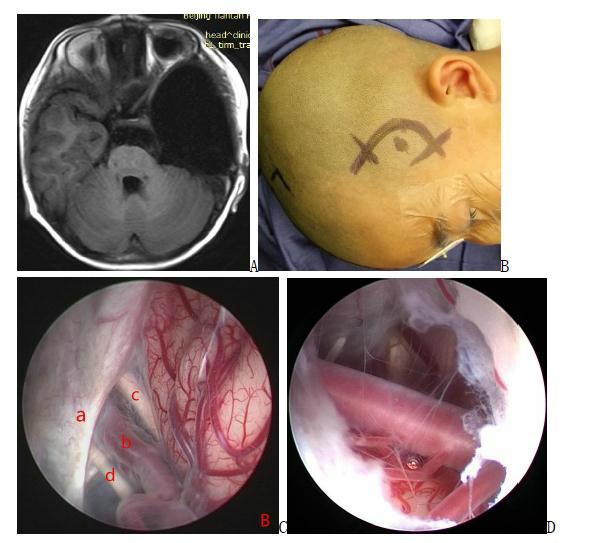

图6. A手术前磁共振图像;B 图示头皮切口;C 手术中截图,内镜下可见囊肿和基底池之间有3个可供选择的造瘘部位:动眼神经和小脑幕缘之间;动眼神经和颈内动脉之间;颈内动脉和视神经之间;D造瘘后可清晰见到下方基底动脉。a:小脑幕 b:颈内动脉 c:视神经 d:动眼神经